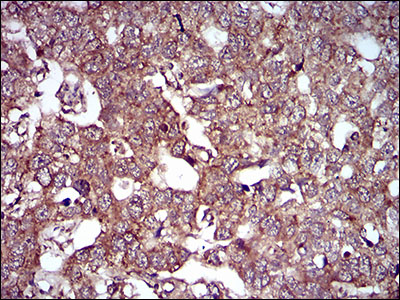

Immunohistochemical analysis of paraffin-embedded human endometrial cancer tissue using anti- caveolin-2 antibody. Counter stained with hematoxylin.

Immunohistochemical analysis of paraffin-embedded human esophageal cancer tissue using anti- caveolin-2 antibody. Counter stained with hematoxylin.